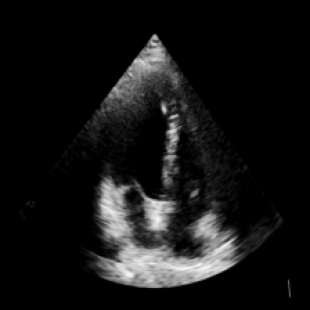

We propose a novel approach that adapts hierarchical vision foundation models for real-time ultrasound image segmentation. Existing ultrasound segmentation methods often struggle with adaptability to new tasks, relying on costly manual annotations, while real-time approaches generally fail to match state-of-the-art performance. To overcome these limitations, we introduce an adaptive framework that leverages the vision foundation model Hiera to extract multi-scale features, interleaved with DINOv2 representations to enhance visual expressiveness. These enriched features are then decoded to produce precise and robust segmentation. We conduct extensive evaluations on six public datasets and one in-house dataset, covering both cardiac and thyroid ultrasound segmentation. Experiments show that our approach outperforms state-of-the-art methods across multiple datasets and excels with limited supervision, surpassing nnUNet by over 20\% on average in the 1\% and 10\% data settings. Our method achieves $\sim$77 FPS inference speed with TensorRT on a single GPU, enabling real-time clinical applications.